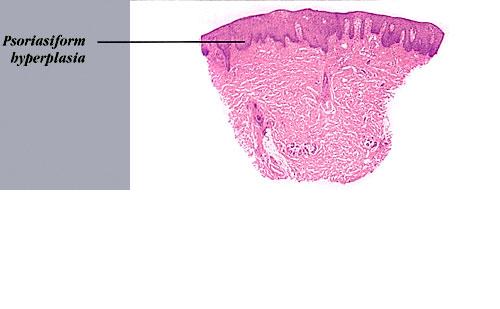

Erythema elevatum diutinum = الحمامى المرتفعة الدائمة Erythema Elevatum Diutinum This rare condition is characterized by persistent, initially red to violaceous and later brown to yellow papules, nodules, and plaques . The lesions, typically distributed symmetrically on the extensor surfaces of the extremities, are initially soft and then evolve into fibrous nodules. Histopathologic Features. In […]